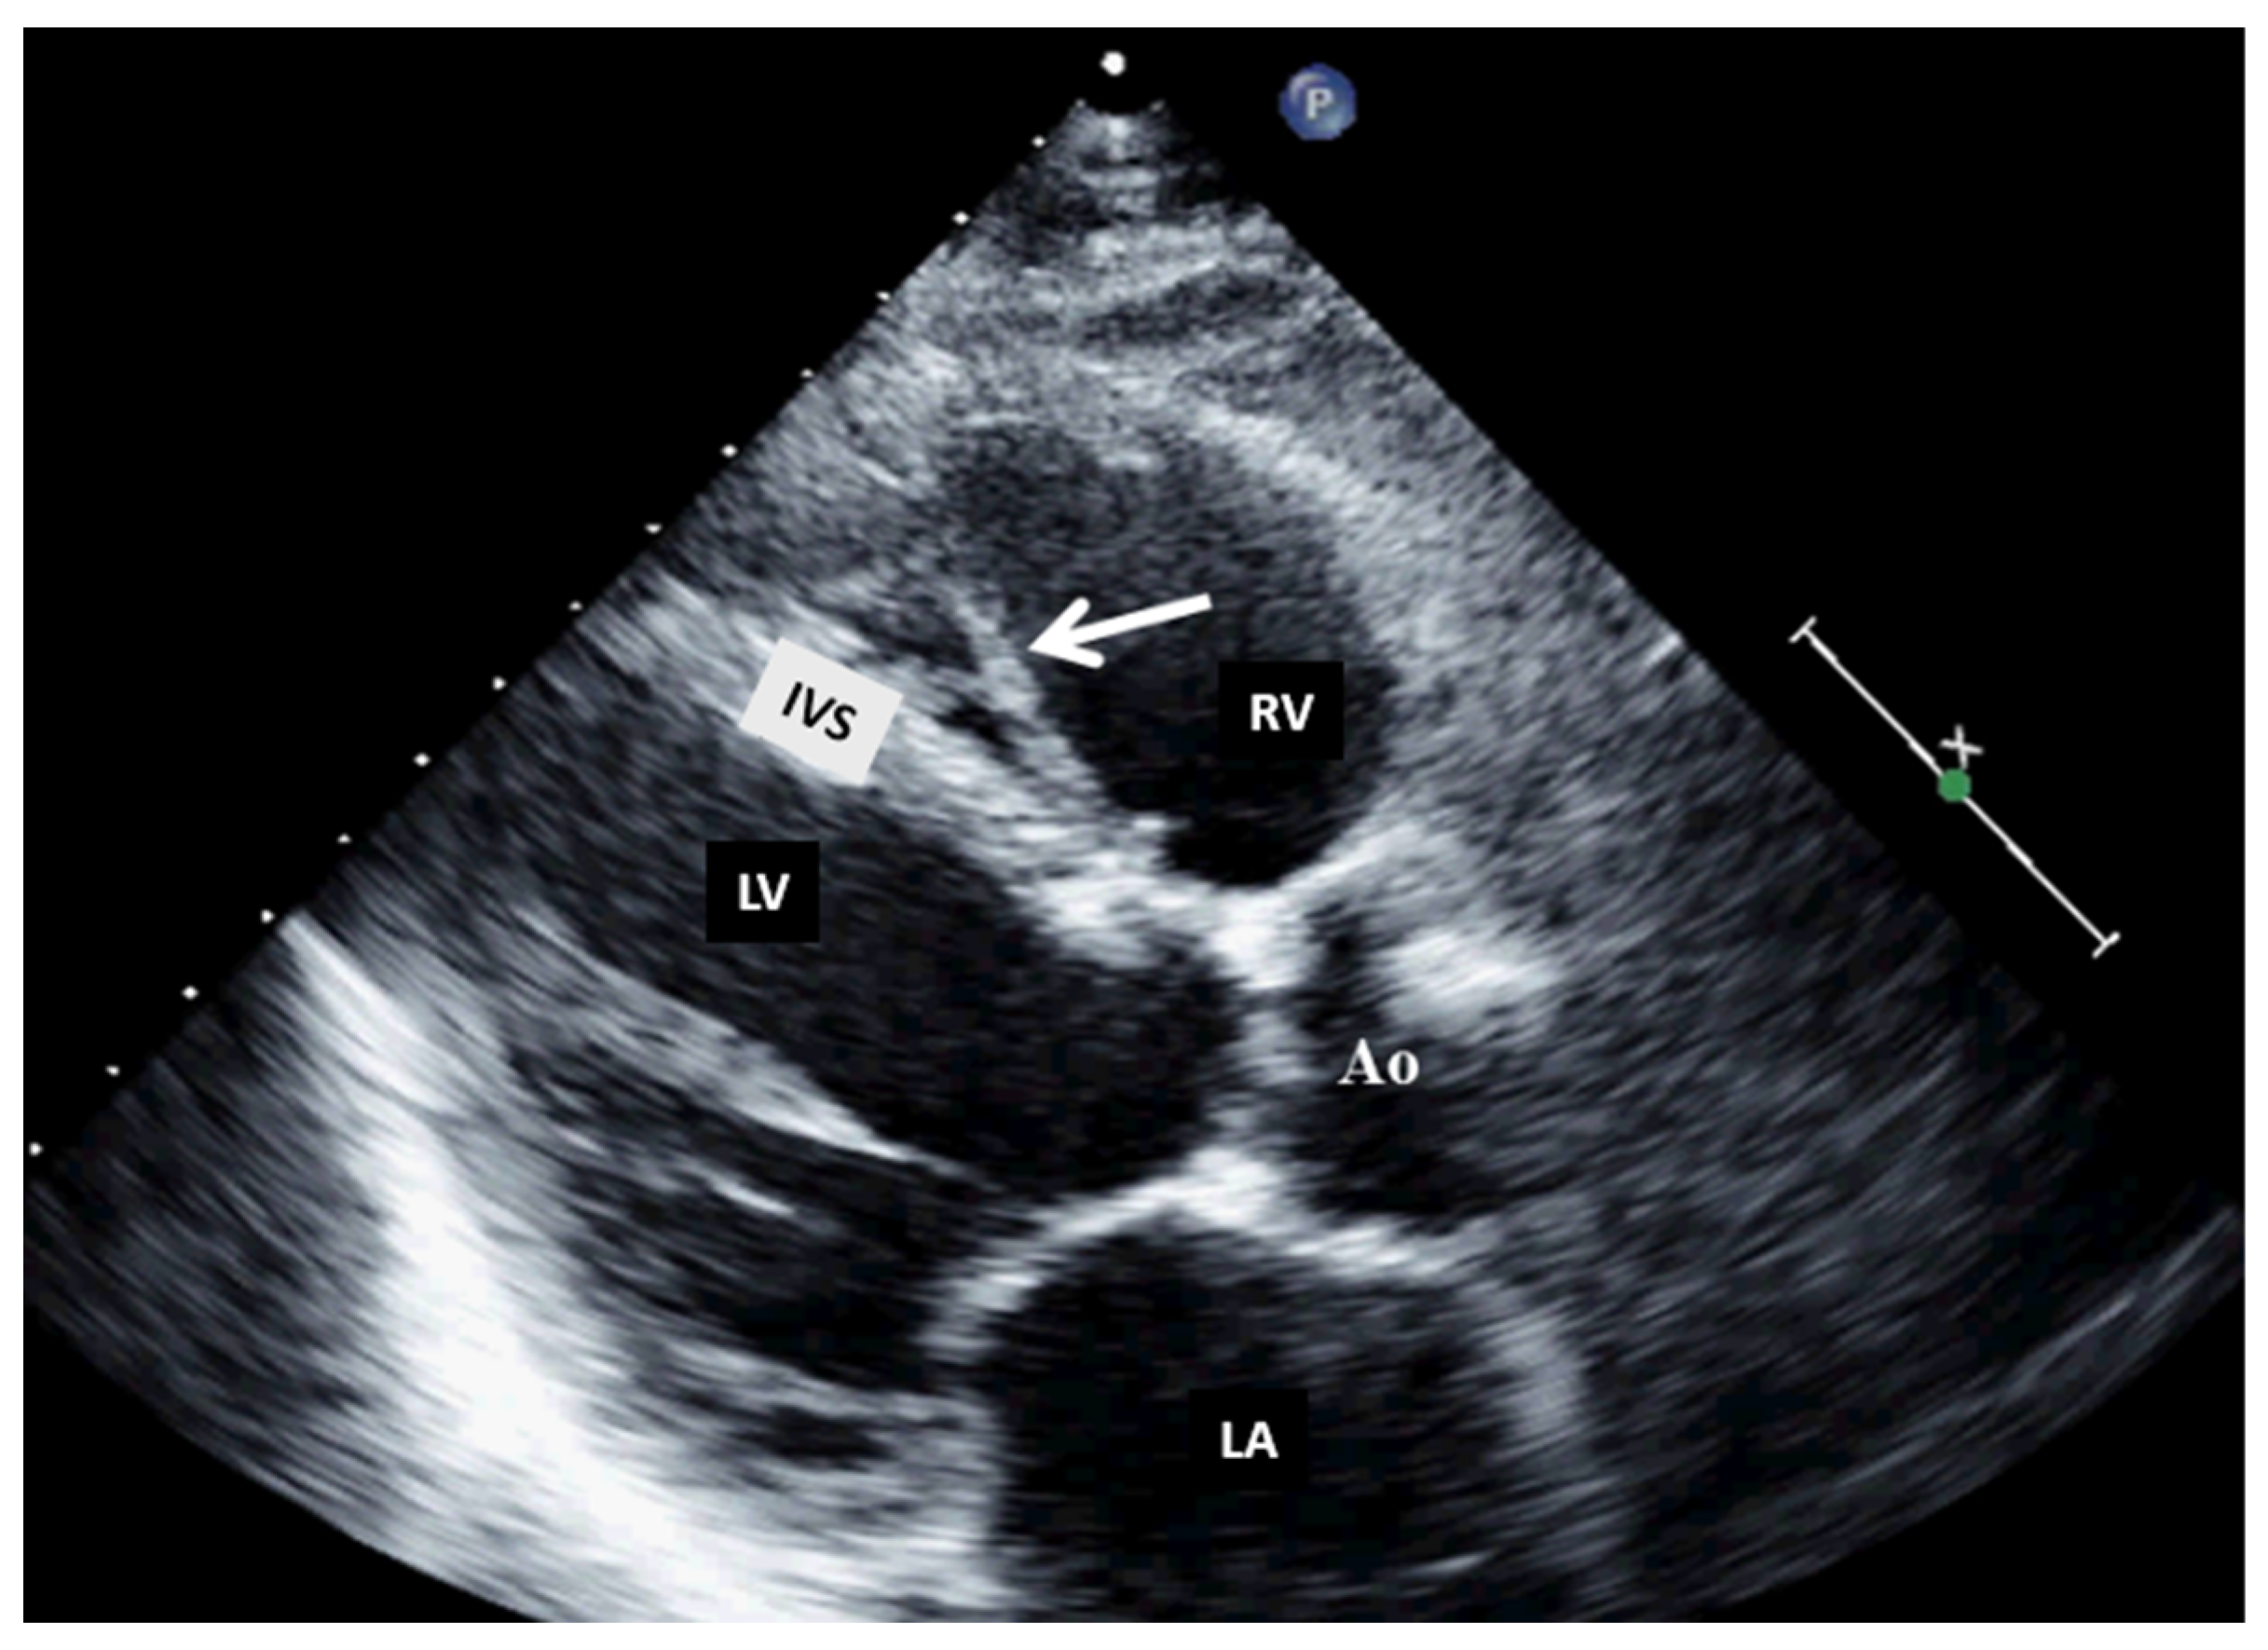

| FIBROMA: This may be associated with fatal arrhythmias, heart failure, and sudden death. Surgical treatment is recommended, regardless of symptoms. | It appears as a large, intramural, well-delimited, non-contractile, solitary solid lesion within the myocardium, with central calcification. | It is described as an intramural, homogenous structure with sharp margins or infiltrative, with central calcification (a common feature of fibromas on CT), and soft-tissue attenuation, frequently without enhancement. | On T1WI, it is an isointense tumor, and on T2WI, it is a hypointense homogenous structure. On LGE, an intense delayed hyperenhancement is observed, without enhancement on resting. | It is usually not necessary, except in cases of suspected malignancy. |